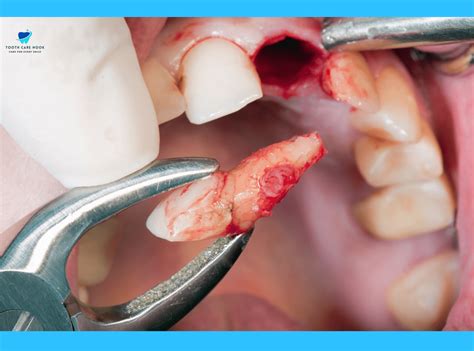

Undergoing a dental extraction is a common procedure, yet the period immediately following the surgery is critical for your recovery. The most vital component of this healing process is the formation and preservation of an after extraction blood clot. This clot acts as a natural bandage over the empty socket, protecting the underlying bone and nerve endings while facilitating the growth of new tissue. If this clot is dislodged or dissolves prematurely, you risk developing a painful condition known as dry socket. Understanding how to protect this clot is essential for a smooth, pain-free recovery.

Following the removal of a tooth, your body immediately triggers a clotting response to stop bleeding. This gelatinous mass is the foundation of your recovery. Without it, the jawbone remains exposed to the oral environment, leading to intense pain that can radiate to your ear, eye, or temple. Protecting the after extraction blood clot is not just about comfort; it is about preventing infection and ensuring the healing progresses at the intended pace.

The clot typically remains in place for 7 to 10 days while the gum tissue begins to close over the site. During this timeframe, the clot undergoes a maturation process, turning from a deep red to a whitish or yellowish color, which is a normal part of the healing cycle. It is important to distinguish between normal healing processes and the actual loss of the clot.